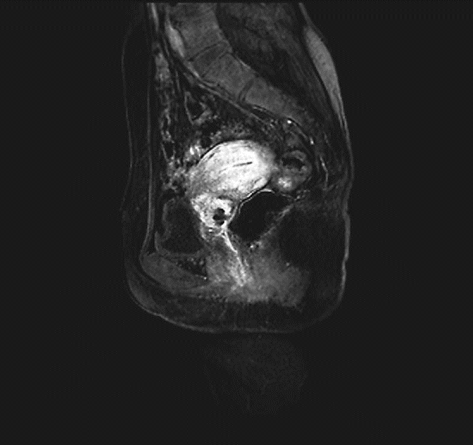

确诊后根据具体情况选择胸部X线或CT平扫、静脉肾盂造影、膀胱镜检査、直肠镜检查、超声检查及盆腔或腹腔增强CT或磁共振、PET-CT等影像学检查。

ⅠB1期宫颈癌MR ⅠB2期宫颈癌MR

ⅡA1期宫颈癌MR ⅡA2期宫颈癌MR

ⅡB期宫颈癌MR ⅢA期宫颈癌MR

ⅢB期宫颈癌MR ⅣB期宫颈癌MR